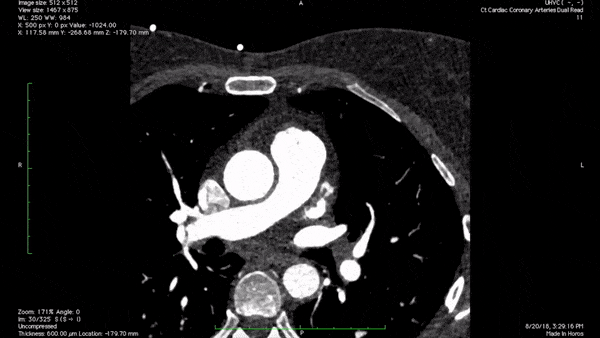

Visualizing your medical data in augmented reality is now possible with MedLens. Simply upload your 3D files or submit a DICOM set and watch your data come to life right before your eyes!